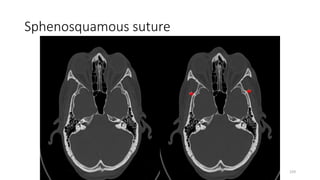

Sphenosquamous suture

SPHENO SQUAMOUS SUTURE